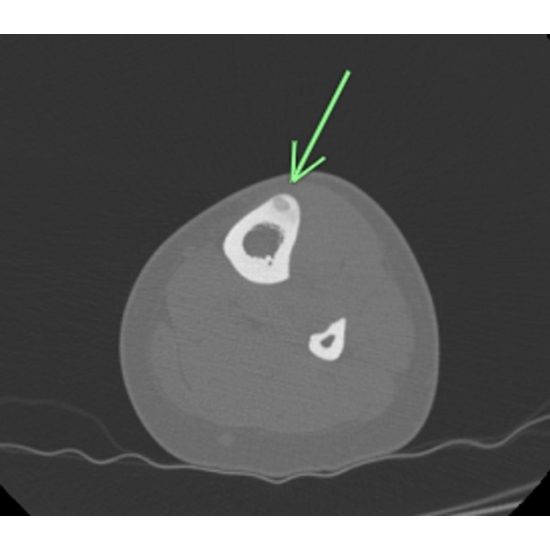

| Hoop Dreams And Bone Nightmares - Page #3 | |||